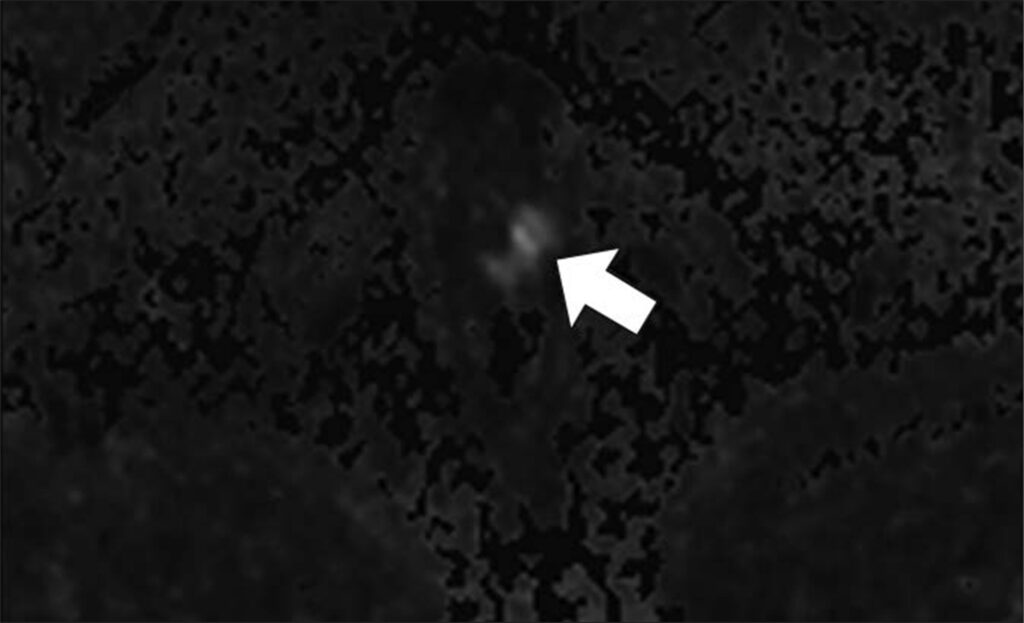

47-year-old man with history of two negative systematic biopsies at another facility and increasing PSA level (most recently, 35.6 ng/mL). Multiparametric MRI was performed for persistent clinical suspicion of clinically significant prostate cancer

Top to Bottom: Axial T2-weighted (Top), axial high-b-value (2000 s/mm2) (Middle), and calculated ADC (Bottom) MR images show left apical anterior central gland lesion (arrow) with very high suspicion of being clinically significant prostate cancer. Lesion is PI-RADS category 5. MRI–transrectal ultrasound fusion biopsy of lesion resulted in pathologic diagnosis of prostatic adenocarcinoma, Gleason 4 + 3 = 7 (grade group 3). Gleason 4 pattern represents 60% of tumor. Prostate volume calculated with MRI is 40 mL.